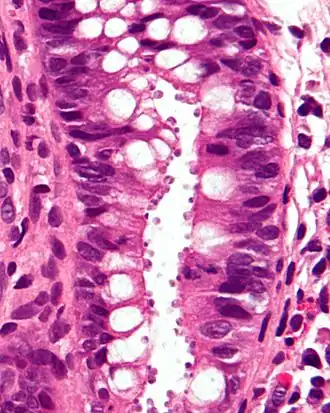

![]() Микрофотография гистологического среза кишечника, демонстрирующая заражённые клетки | |

Существуют различные диагностические тесты для выявления криптоспоридиоза. Они включают в себя микроскопирование, окрашивание и обнаружение антител. Микроскопия используется для обнаружения ооцист в фекалиях пациента[9]. Для концентрации и выявления спороцист в пробе кала используются модифицированный метод центробежной плавучести сульфата цинка и метод плавучести сахара Шелтера[14]. Методы окраски включают окраску на кислото-устойчивые микроорганизмы, придающую ооцистам красный цвет. Также может быть использовано окрашивание красителем Гимза. Часть тонкой кишки может быть окрашена гематоксилином и эозином, что выявляет ооцисты, прикреплённые к эпителиальным клеткам[6]. Кроме того, применяется люминесцентная микроскопия проб, окрашенных аурамином[9].